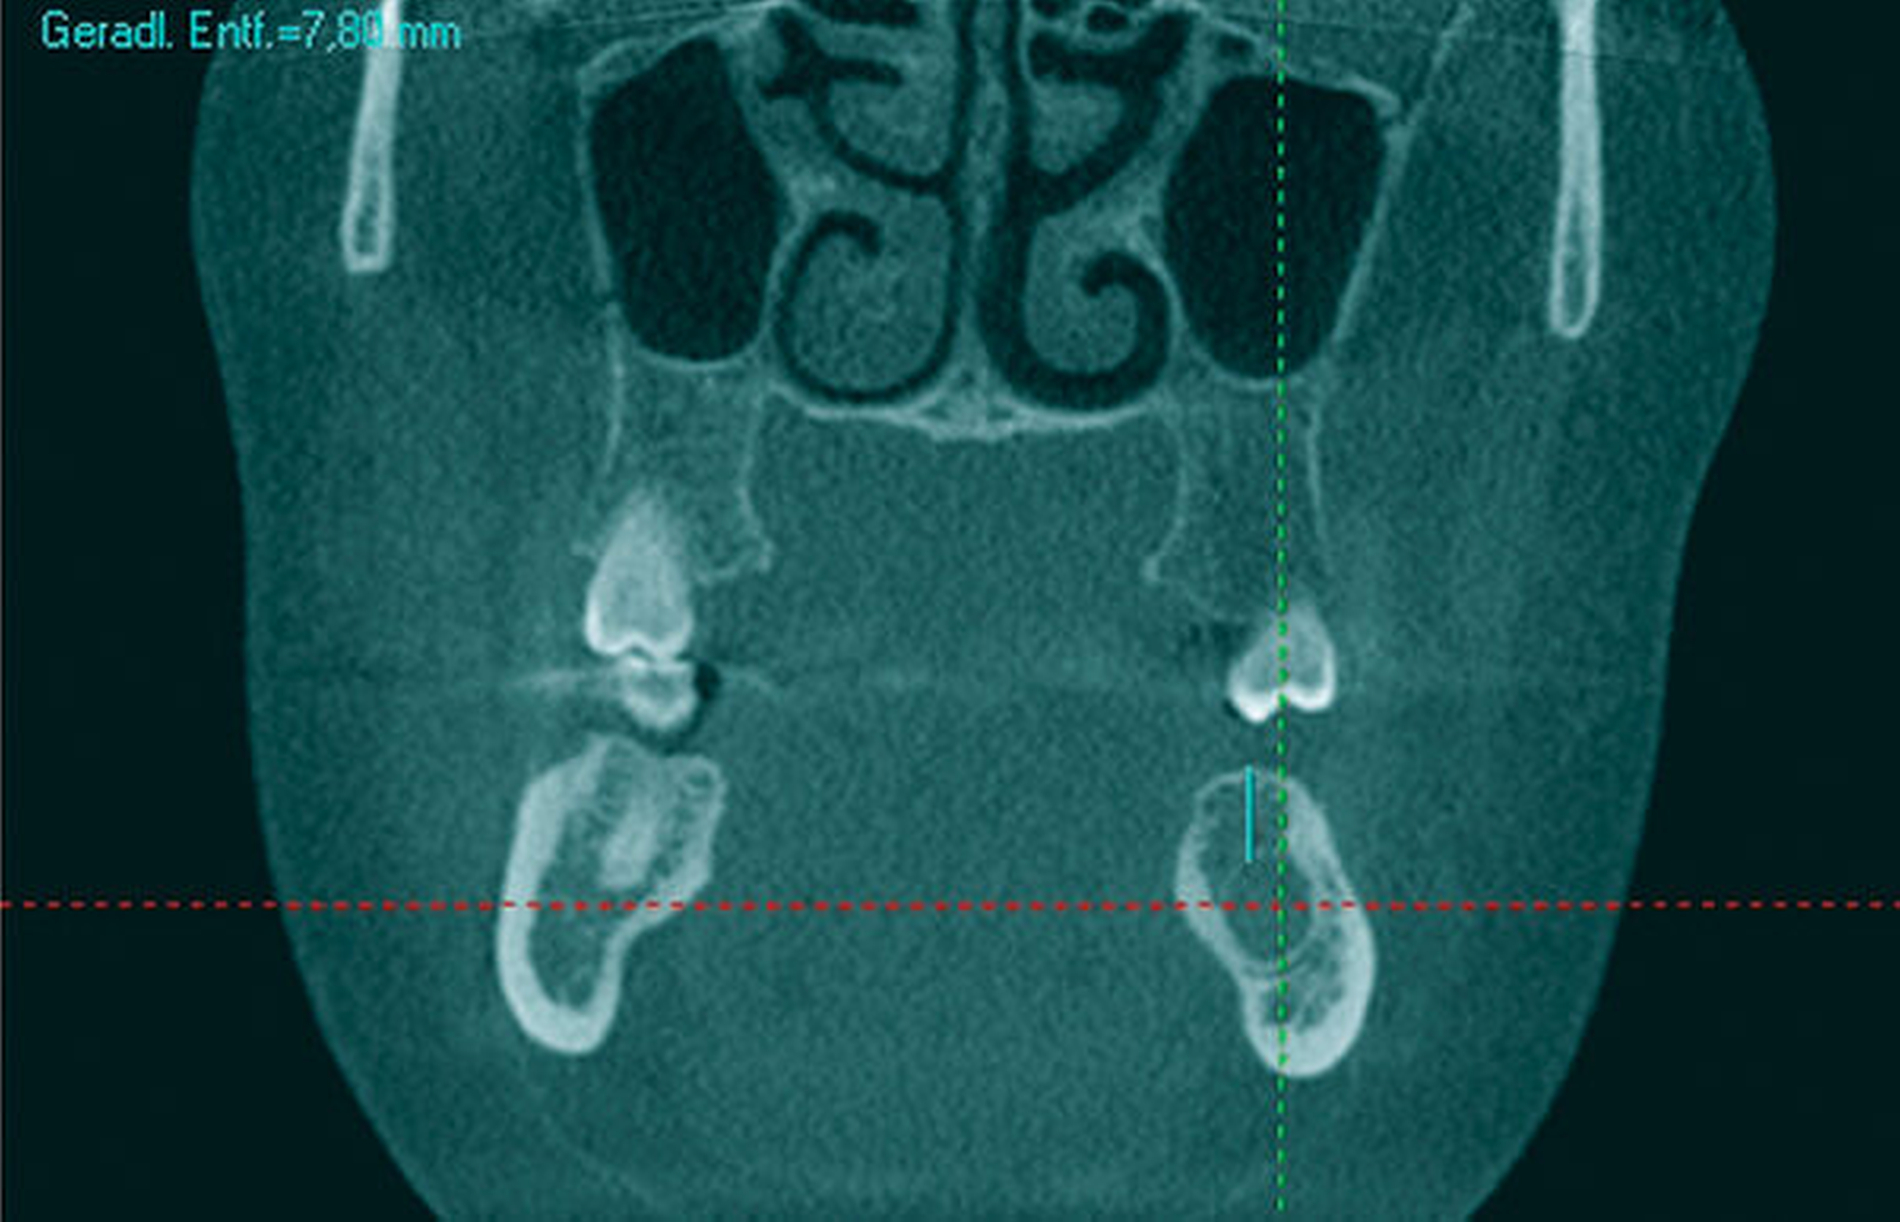

Aufgrund der tiefen intraossären Lage ohne direkten Zahnbezug oder andere klare Orientierungspunkte wurde zur gezielten Ansteuerung auf Basis des DVT-Datensatzes eine Osteotomie-Schablone 3-D-gedruckt (Material: MED 610, Drucker: EDEN 260V, Stratasys), die den Osteotomiezugang genau verschlüsselte (Abbildung 3a). Intraoperativ konnte dadurch die Keratozyste gezielt entfernt werden, ohne dass eine großflächige Osteotomie notwendig war oder ein erhöhtes Risiko für die Verletzung des N. alveolaris inferior bestand (Abbildung 3b). Der Befund wurde zystekotomiert und die Knochenhöhle zusätzlich ausgefräst (Abbildung 4). Auch die postoperative radiologische Kontrolle bestätigte eine optimale Lage der Osteotomie (Abbildung 5). Die postoperative Heilung war unproblematisch, drei Jahre nach dem Eingriff ist die Patientin rezidivfrei (Abbildung 6).

Im vorliegenden Fall wäre aufgrund der tief intraossären Lage ohne Osteotomie-Schablone auf jeden Fall eine großflächige Osteotomie notwendig gewesen, um die Rezidiv-Keratozyste aufzufinden. Zusätzlich zum damit einhergehenden Verlust an Knochenhartsubstanz besteht bei einer solchen explorierenden Osteotomie des lateralen Unterkiefers ein größeres Risiko einer Nervverletzung. Um dies zu vermeiden, verschlüsselt die 3-D-gedruckte Schablone sicher die Position einer nervfernen Osteotomie, was die Gefahr für eine Schädigung des Nervens reduziert. Mit einer chirurgischen Schablone kann eine erhöhte Sicherheit für den Operateur und den Patienten erzielt werden [Nickenig et al., 2012].

Die Basis für eine schablonengestützte Chirurgie ist ein dreidimensionaler Röntgendatensatz, der in eine 3-D-Datei, zum Beispiel im „.stl“-Format (standard tesslation language), überführt wird, und an dem dann die virtuelle Operation simuliert werden kann [Goetze et al., 2017; Goetze et al., 2020]. Nach virtuellem Festlegen der gewünschten Osteotomie wird diese dann über eine computerassistiert gestaltete digitale Schablone verschlüsselt. Dies nutzt die patienteneigene Anatomie zur optimalen Ausformung der Positionierung als Modell. Der Datensatz wird exportiert und mit einem biokompatiblen Material, zum Beispiel mittels 3-D-Druck, gefertigt. Die daraus entstandene Schablone kann dann nach entsprechender Desinfektion beziehungsweise Sterilisation im Patienten angewandt werden [Goetze et al., 2017].